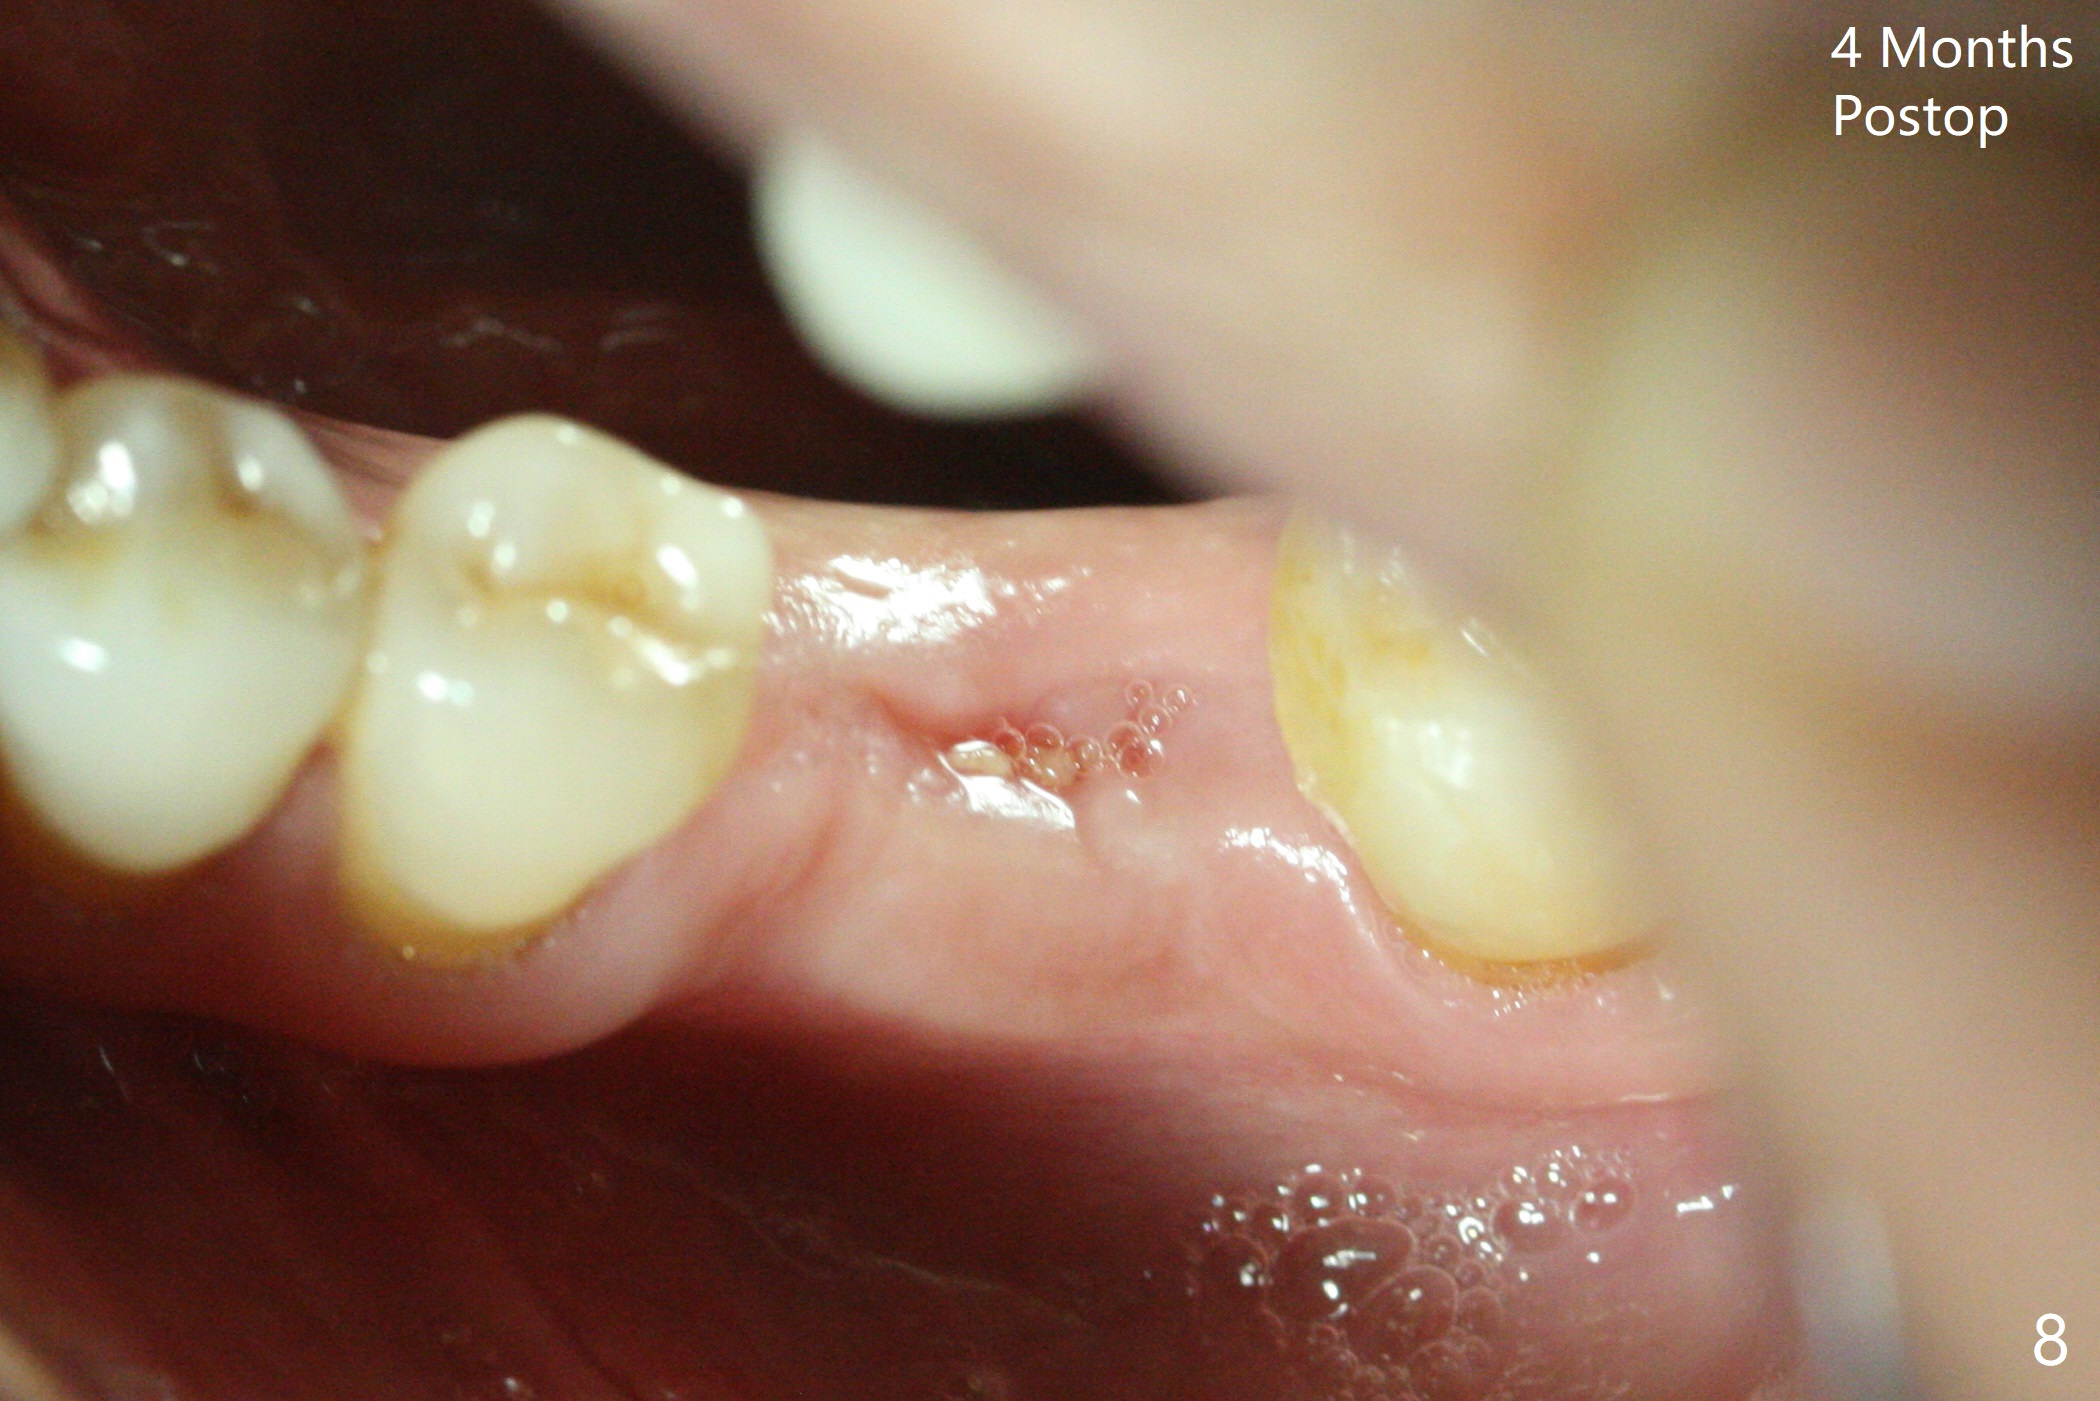

Extraction of the tooth #19 with large PARL (Fig.1,2) confirms the loss of buccal plate, but the crestal bone exists. After failure to place an implant in the middle socket with removal of the lingual septal bone, socket preservation is done with PRF and sticky bone (Fig.3). There is possibility to place a ~4 mm implant in the mesial socket (Fig.4). Or just drop a 5x11 mm Bicon Implant into the large socket, surrounded by sticky bone. When periodontal dressing is removed 18 days postop, the bone graft seems to remain to be "sticky" yellowish, while the granulation tissue has started to grow into the center of the socket from the previously buccal and lingual furcae (Fig.5 reddish). Granulation tissue seems to cover the bone graft (Fig.6), although there is smells when the periodontal dressing is removed. Bone height reduces nearly 3 months postop (Fig.7). The buccal plate collapses (Fig.8), but there seems no further bone loss 4 months postop (Fig.9). Because of buccal plate loss, an implant will be placed lingually with guide (Fig.10-12 green). Bone graft may be placed buccally after implant placement with probing.